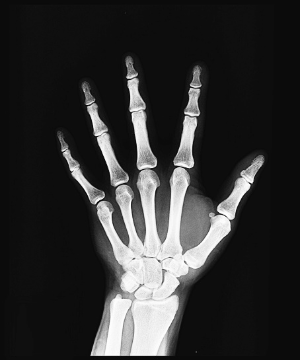

3. 관절 부음

류마티스 관절염은 주로 양쪽의 대칭적인 작은 관절을 표적으로 합니다. 손가락, 발가락의 관절, 손목, 발목, 팔꿈치, 무릎 등이 부어오르고 아프며 따끔거립니다. 이런 부음은 염증으로 인해 관절 주변의 활막이 팽창하고 관절액이 증가하기 때문입니다.